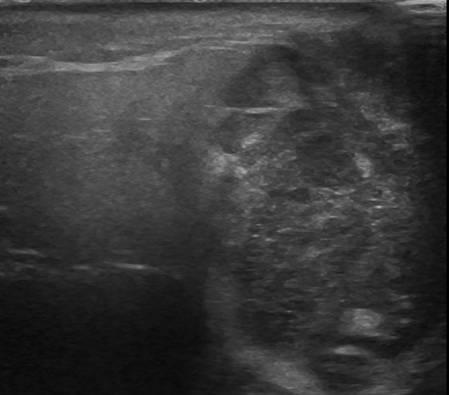

U tuyến nước bọt

» Thông tin: Nam giới – 79 tuổi.

» Lâm sàng: Khối vùng mang tai / K thực quản.

# Di căn tuyến nước bọt mang tai.